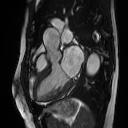

Representation learning evaluation via reconstruction.

We first evaluate reconstruction using only SA sequences, only LA sequences, and all available views in pre-training. The quantitative results and reconstructed CMR images are shown in Appendix Table 3 and Fig. 4. The superior results of all-view reconstruction to that of using only limited spatial planes imply the benefit of involving all-view spatiotemporal information for whole-heart representation learning. Incorporating different views can help the model build spatial knowledge of the heart and therefore enhance the representation/reconstruction.

Appendix 0.A Supplementary

Table 3: Reconstruction PSNR (dB) for SA and LA views. From left to right it shows the PSNR of our model trained with only SA 2D+T planes, only LA 2D+T planes, and all available multi-view planes separately.

Eval. Input SA LA ALL

SA 26.20±0.84subscript26.20plus-or-minus0.8426.20_{\pm 0.84} N.A. 31.08±0.86subscript31.08plus-or-minus0.86\mathbf{31.08_{\pm 0.86}}

LA N.A. 25.11±1.48subscript25.11plus-or-minus1.4825.11_{\pm 1.48} 28.60±1.50subscript28.60plus-or-minus1.50\mathbf{28.60_{\pm 1.50}}

GTSA/LA View OnlyAll Planes IncludedRefer to captionRefer to captionRefer to captionRefer to captionRefer to captionRefer to caption

Figure 4: Reconstruction samples in the pre-training phase. The second column shows reconstructions with input planes from a single view (SA/LA only), while the last column shows the reconstructions with planes from both views included.